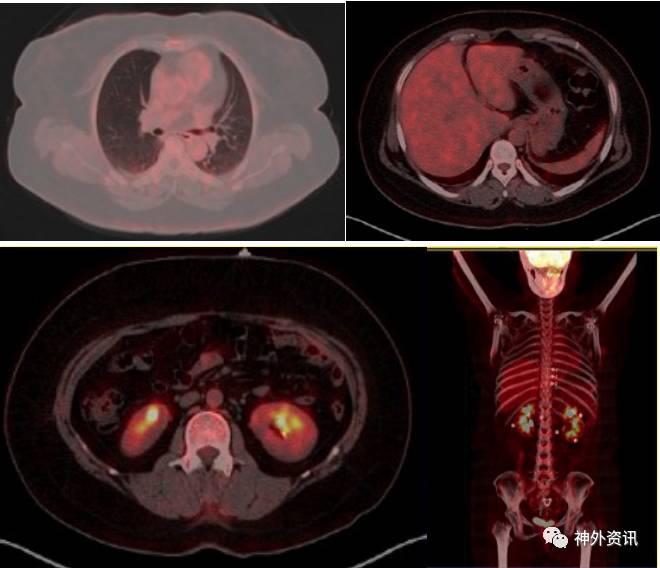

全身PET/CT显像示:①双侧额叶、顶叶、颞叶、枕叶,双侧基底节、丘脑、小脑放射性分布对称,未见明显放射性摄取增高或减低灶。②双侧胸腔少量积液;③脂肪肝;回盲部肠壁代谢稍高,提示炎症;④左肾小结石;子宫内节育环;右侧附件区囊性病变考虑(图3)。

图3. PET/CT:颅内未见明显放射性摄取增高或减低灶,回盲部肠壁代谢稍高,提示炎症,左肾小结石,右侧附件区囊性病变考虑。